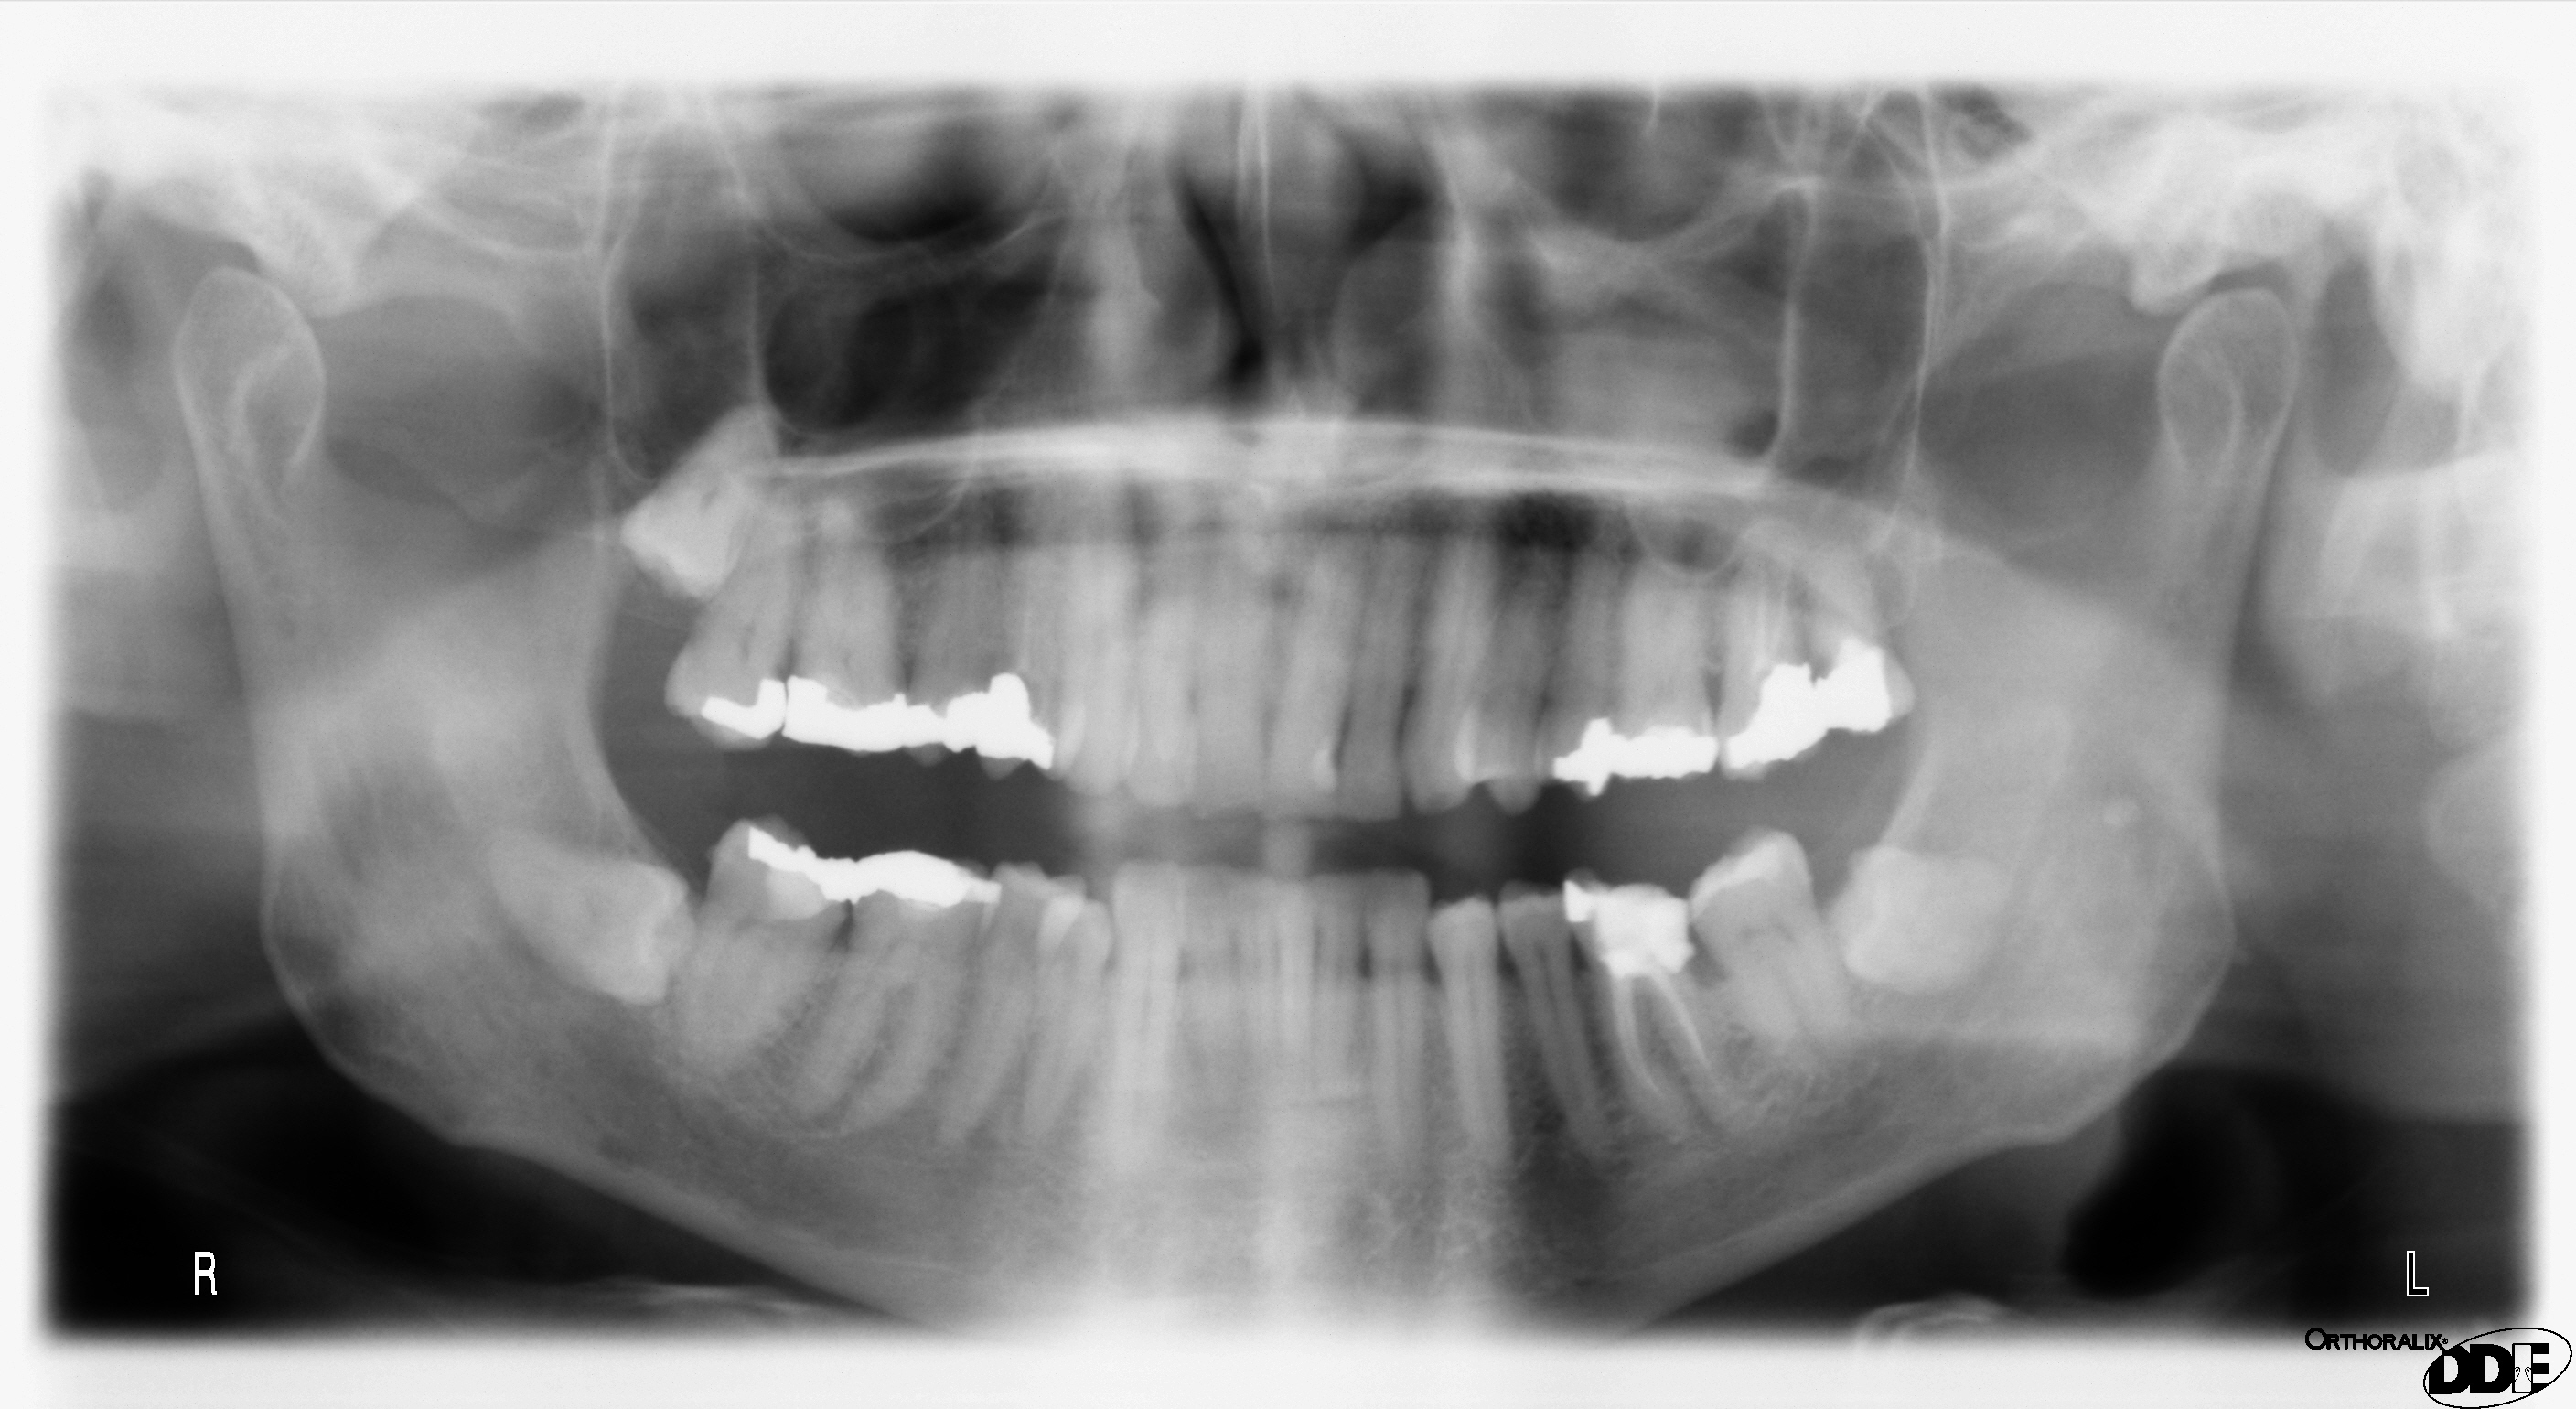

After months in hiding, “butcher dentist” Jacobus van Nierop has appeared in court to face charges of mutilation from more than 100 patients. He is alleged to have used unnecessary procedures, improper equipment and heavy anesthetics to inexplicably remove healthy teeth and render patients with agonizing results. One former patient described how van Nierop, 51, pulled out eight teeth in one sitting. The patient then bled for three days straight. Another patient said van Nierop left “pieces of flesh hanging” after removing a tooth. The former dentist faces charges of defrauding French social security and “wilful violence causing mutilation and permanent injury.”